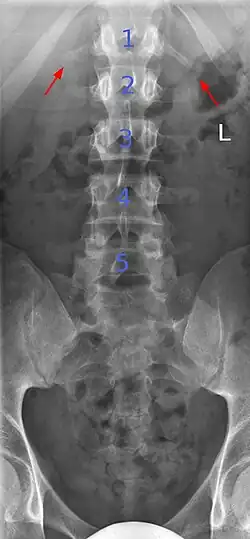

Sacralization of the fifth lumbar vertebra (or sacralization) is a congenital anomaly, in which the transverse process of the last lumbar vertebra (L5) fuses to the sacrum on one side or both, or to ilium, or both. These anomalies are observed in about 3.5 percent of people, and it is usually bilateral but can be unilateral or incomplete (ipsilateral or contralateral rudimentary facets) as well. Although sacralization may be a cause of low back pain, it is asymptomatic in many cases (especially bilateral type). Low back pain in these cases most likely occurs due to biomechanics. In sacralization, the L5-S1 intervertebral disc may be thin and narrow. This abnormality is found by X-ray.

Congenital block vertebra in the lumbar spine (partial vertebrae 3 and 4). The rear portion of the disc still exists. -

Congenital block vertebra of the lumbar spine. CT volume rendering. -

Congenital block vertebra of the lumbar spine. CT volume rendering.